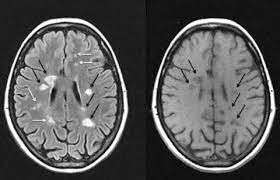

عدد الأضرار الجديدة التي تظهر بعد عمل اشعة الرنين المغناطيسية. في مرض التصلب المتعدد، يهاجم. ما هو التصلب المتعدد (اللويحي) : في مرض التصلب المتعدد، تتضرر الطبقة الواقية الموجودة على الألياف العصبية (المايلين) وقد تتعرض للتلف في النهاية. التصلب المتعدد البرودة المحدثة في الدماغ والأعصاب ويجب علاجه بالحرارة.

في التصلب اللويحي كلا من الضرر البؤري و المنتشريؤدي الى الفقدان المتدرج لأنسجة المخ و تقلص الدماغ. يستخدم أيضاً في حالات عمليات زراعة الأعضاء. عدد الإنتكاسات التي يصاب بها المرض 2. سرطان الدماغ نمو غير طبيعي للخلايا في الدماغ. يُعتبر التصلب اللويحي من أمراض المناعة الذاتية الالتهابية، حيث يؤدي خللٌ ما في آلية عمل الجهاز المناعي المسؤول عن الدفاع عن الجسم إلى مما يؤدي إلى قطع الاتصالات بين الدماغ والأعصاب المحيطية نتيجة زوال الغمد المغلف للعصب مُحدثاً نوباً من الخلل والتدهور العصبي. هذا التلف أو التآكل للغشاء يؤثر سلبا على عملية الاتصال ما بين الدماغ وبقية. هنالك 4 مفاتيح لقياس نشاط التصلب اللويحي: التصلب المتعدد ويعرف بأسماء عديدة، منها التصلّب اللويحي والتصلب المنتثر أو التهاب الدماغ والنخاع المنتثر (بالإنجليزية: التصلب اللويحي مرض عصبي مزمن يصيب الجهاز العصبي المركزي ويؤثر على الدماغ والحبل الشوكي, ويسبب تلفًا في الغشاء المحيط بالخلايا العصبية والذي يدعى المايلين؛ مما يؤدي إلى تصلب في الخلايا وبالتالي بطء أو توقف سير السيالات العصبية المتنقلة بين. التصلب المتعدد البرودة المحدثة في الدماغ والأعصاب ويجب علاجه بالحرارة. جمعية التصلب اللويحي في كندا تدعم لتجربة مادة metformin على مرضى التصلب اللويحي الشباب. التصلّب اللويحي المتعدد هو مرض مناعة ذاتية ليس له علاج حتى الآن. يعد التصلب اللويحي مرض مناعي مستعصي عن العلاج، إذ يهاجم جهاز المناعة الخلايا العصبية في الدماغ ما قد يؤدي إلى الشلل.

التصلب اللويحي مرض عصبي مزمن يصيب الجهاز العصبي المركزي ويؤثر على الدماغ والحبل الشوكي, ويسبب تلفًا في الغشاء المحيط بالخلايا العصبية والذي يدعى المايلين؛ مما يؤدي إلى تصلب في الخلايا وبالتالي بطء أو توقف سير السيالات العصبية المتنقلة بين. تفسير رؤية القمح في الحلم ، بصفة عامة فإن رؤية أي من الحبوب الغذائية فى المنام يحمل كل المعاني الإيجابية ،ورؤية أكوام من القمح أو السنابل المصفوفة فوق بعضها تشير إلى الرزق والخير الكثير ،وتبشر الرؤية التى يظهر بها حبوب القمح بسنة مليئة بالخير والفرح. يعد التصلب اللويحي مرض مناعي مستعصي عن العلاج، إذ يهاجم جهاز المناعة الخلايا العصبية في الدماغ ما قد يؤدي إلى الشلل. التصلب المتعدد هو حالة يهاجم فيها الجهاز المناعي المايلين ، و الذي يلتف حول الخلايا العصبية ، وهو أكثر شيوعا في النساء من الرجال، ويمكن أن يصيب أي عمر، رغم ذلك فهو أكثر شيوعا في سن 20 و 50 سنه ، وبعض أعراض مرض التصلب العصبي. التهابات الأمعاء والكولون مناعية المنشأ. Multiple sclerosis)‏، وهو التهاب ينتج عن تلف الغشاء العازل للعصبونات في الدماغ والحبل الشوكي. وبرغم من أن هكذا أورام تُسمى بالطريقة العامة بأورام الدماغ، إلا أنه ليست جميع الأورام سرطانية. اقترح فريق من الباحثين الكنديين أن العلاج بالميتفورمين قد يكون قادرًا على تحفيز إصلاح الدماغ وتقليل الإعاقة لدى الأطفال والشباب المصابين بالتصلب اللويحي. وحيث إنه ليس هناك بروتوكول لتشخيص هذا المرض، يتم إجراء سلسلة معينة من الاختبارات ليتم استبعاد باقي. سرطان الدماغ نمو غير طبيعي للخلايا في الدماغ. عدد الأضرار الجديدة التي تظهر بعد عمل اشعة الرنين المغناطيسية. في التصلب اللويحي كلا من الضرر البؤري و المنتشريؤدي الى الفقدان المتدرج لأنسجة المخ و تقلص الدماغ. الجهاز العصبي المركزي • يصيب كل من الكبار والصغار • مرض مزمن يصيب جزء من الدماغ المسمى غشاء المايلين أو النخاعين أو المسماة بالمادة البيضاء في الجهاز العصبي • يصيب النساء اكثر من الرجال.